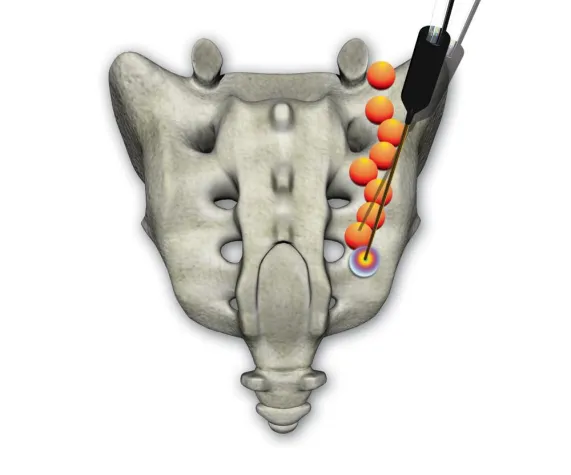

Der Eingriff erfolgt bei sterilen Bedingungen unter Röntgendurchleuchtung in örtlicher Betäubung, damit der Patient während der Behandlung ansprechbar ist und über seinen Schmerzzustand direkt Auskunft geben kann. Nachdem eine Führungskanüle exakt am Zielpunkt platziert wurde, schaltet ein lokales Betäubungsmittel den Nerv aus. Dann erzeugt die Sonde mittels Radiofrequenzen Wärme. Das Besondere ist die Form der Sonde, die eine kugelförmige Ausbreitung des Stroms ermöglicht und nacheinander mehrere Punkte, so genannte Läsionen, setzt. Dieser Vorgang kann solange wiederholt werden, bis das gewünschte Ergebnis erzielt ist. Die Risiken sind weitaus geringer als bei einer herkömmlichen Operation. Durch die konstante visuelle Kontrolle, die Wasserkühlung und die Ansprechbarkeit des Patienten ist eine Verletzung der umliegenden Nerven, Gefäße und Weichteile nahezu ausgeschlossen. Die Einstichstelle für die Sonde ist so minimal, dass sie lediglich steril mit einem Pflaster abgedeckt wird und eine Naht überflüssig ist.

Die Radiofrequenz-Neurotomie lässt sich auch bei Patienten mit tiefen Kreuzschmerzen, wie bei Beschwerden am Iliosakralgelenk oder der Lendenwirbelsäule anwenden. Sofern eine konservative Therapie keine Entlastung bringt, hilft hier die perkutane Denervierung, also die Behandlung durch die Haut mittels der speziellen Sonde.